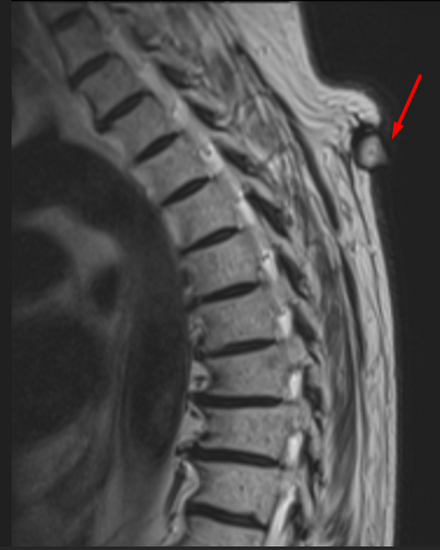

🔹 MRI findings (current):

T1: Hypointense

T2: Mildly hyperintense (not as bright as pure fluid, due to keratin/debris)

Capsule: Thin, well-defined

Base: Sitting on the subcutaneous fat

Protrusion: “Beak/drop-shaped tip” extending from dermis into subcutis

MRI: Beak-shaped protrusion + typical signal intensity